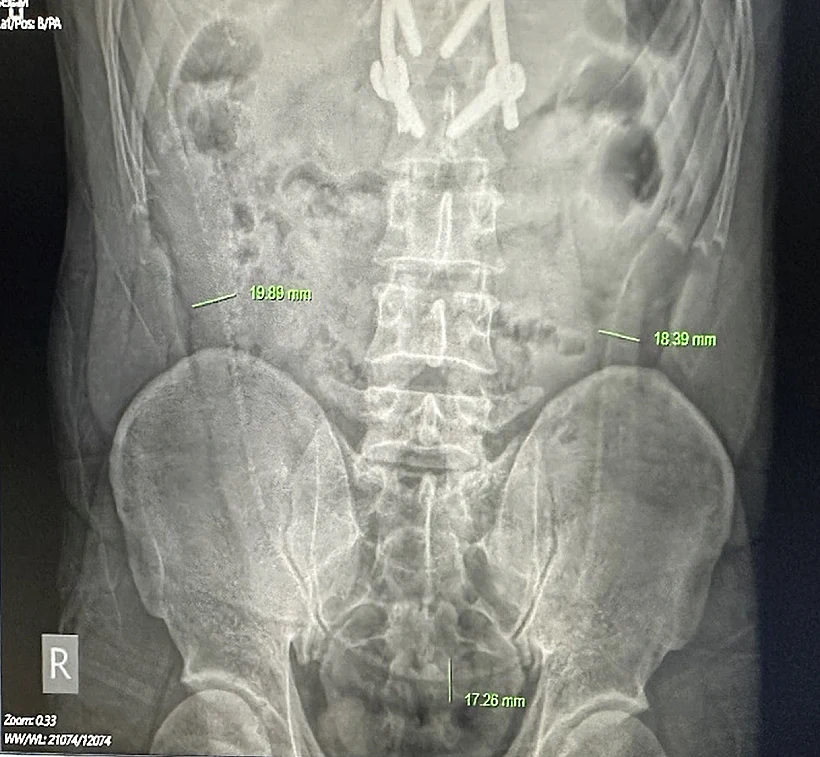

צילומי הרנטגן חשפו כי אכן ישנו צלופח ארוך המשתרע על פני בטנו של המטופל. ההליך הניתוחי בוצע בראשות ד״ר לה ניאט הווי, סגן מנהל המרכז לניתוחי המעי הגס. תחילה תכננו הרופאים לבצע במטופל אנדוסקופיה על מנת להסיר את הצלופח, אך במהלך ההליך הופתעו הרופאים לגלות לימון בעובי 4 ס״מ תקוע בפי הטבעת של המטופל. הלימון חסם את המסלול ולכן לא ניתן היה להמשיך לבצע את האנדוסקופיה.